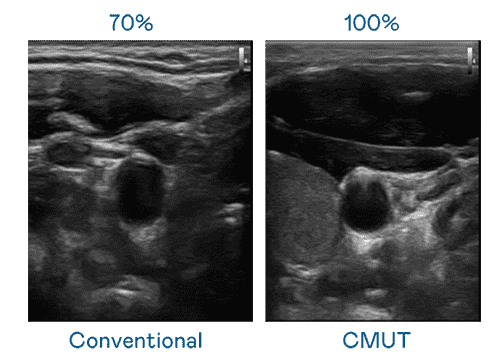

CMUT 技术是一种用电容式微机电元件来产生超音波讯号的技术。。与传统 PZT 压电式技术相比,,CMUT 频宽增加 30%,,,,更宽频的超音波讯号让影像解析度大幅提升,,,,是实现高影像品质医疗超音波扫描、、、、促进精准医疗发展的关键技术。。。。

大频宽带来超清晰影像

超音波影像的解析度高低,,,,首先取决于探头能发出的讯号频宽。。。。传奇国际 CMUT 可提供高清晰的超音波讯号,,,,提供高频宽、、、、高灵敏度、、、影像纹理细节更高的超音波影像,,,,协助医护人员缩短影像判读时间及利用精准的医疗影像进行诊断。。